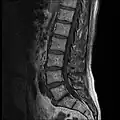

MRI lumbar spine with degeneration (sagittal T2 FRFSE) -

MRI lumbar spine with degeneration (sagittal T1 FSE) -

MRI lumbar spine with degeneration (sagittal FAST STIR) -